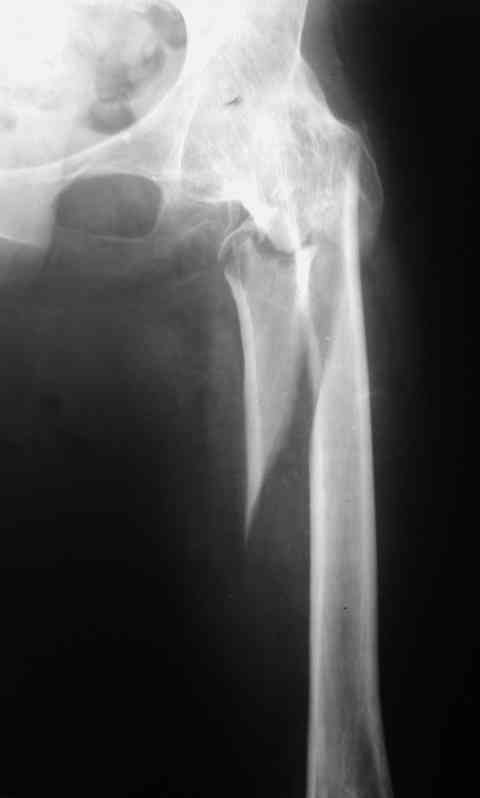

Re: перелом бедра+анкилоз тазобедренного сустава

Спасибо за совет и комментарии. Выбор остановили на длинной пластине DCP. Нам показалось, что в нашей ситуации так будет прочнее, по сравнению с клинковой пластиной или DHS.